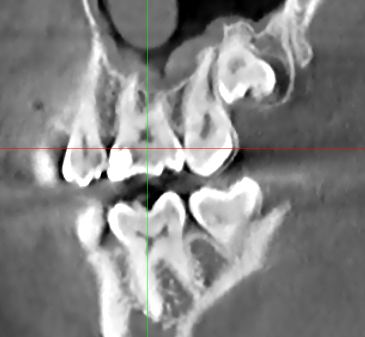

На 6 жевательном зубе справа на верхней челюсти в 2020 году поставлена пломба. Фото прилагаю. На КТ от 2024 года я сам нашел полость под пломбой, это вторичный кариес? Врач который смотрел КТ об этом не упоминал. Еще вопрос зуб же не депульпированный?

Все эти годы зуб не беспокоил. КТ скрины прилагаю.